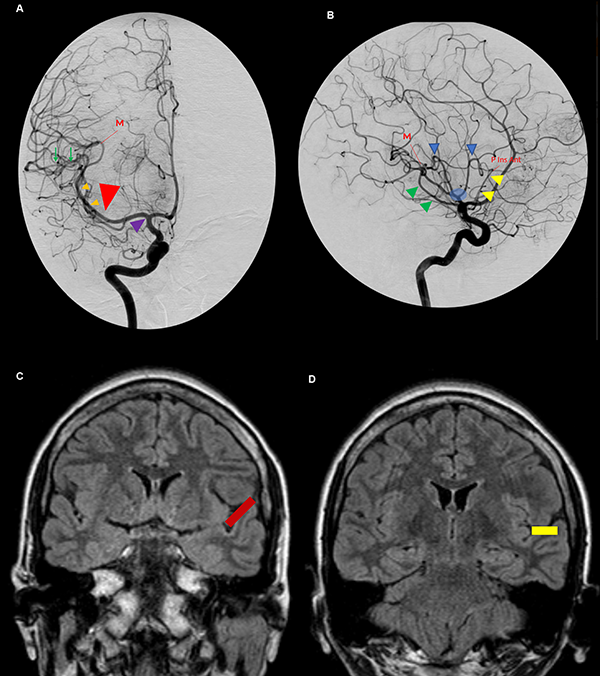

Figura 11: A. Vista anteroposterior de una angiografía carotídea derecha. El uncus (cabeza de flecha violeta) se relaciona anteriormente con el segmento proximal de M1. El ápex uncal apunta hacia la bifurcación carotídea. Inmediatamente distal al genu de la ACM se ubica la pars triangularis (cabeza de flecha roja grande). Las pequeñas cabezas de flecha naranjas indican el segmento M2 de la ACM y, consecuentemente, la corteza insular. El punto M se define como el punto donde el ramo más posterior de M2 cambia de sentido alejándose de la ínsula hacia el opérculo, en relación estrecha con el extremo posteromedial del giro de Heschl. La ínsula se proyecta desde el genu de la ACM hasta el punto M. Las ramas de M3 sobre el plano temporal tienen un curso recto (flechas verdes). B. Vista lateral de la misma angiografía. Se identifica el triángulo silviano. Su borde anterior (cabeza de flecha amarillo) y superior (cabezas de flecha azul) lo marcan los loops de M2. Su borde inferior lo indica el tronco inferior de M2 cursando por el surco limitante inferior insular (cabeza de flecha verde). Los troncos postbifurcación se ramifican cerca del polo insular y el ápex (círculo celeste). C y D. Vistas coronales de una RMN. El plano polar tiene una dirección oblicua inferior (barra roja) (C) y el plano temporal una dirección recta (barra amarilla) (D). P Ins Ant: punto insular anterior.